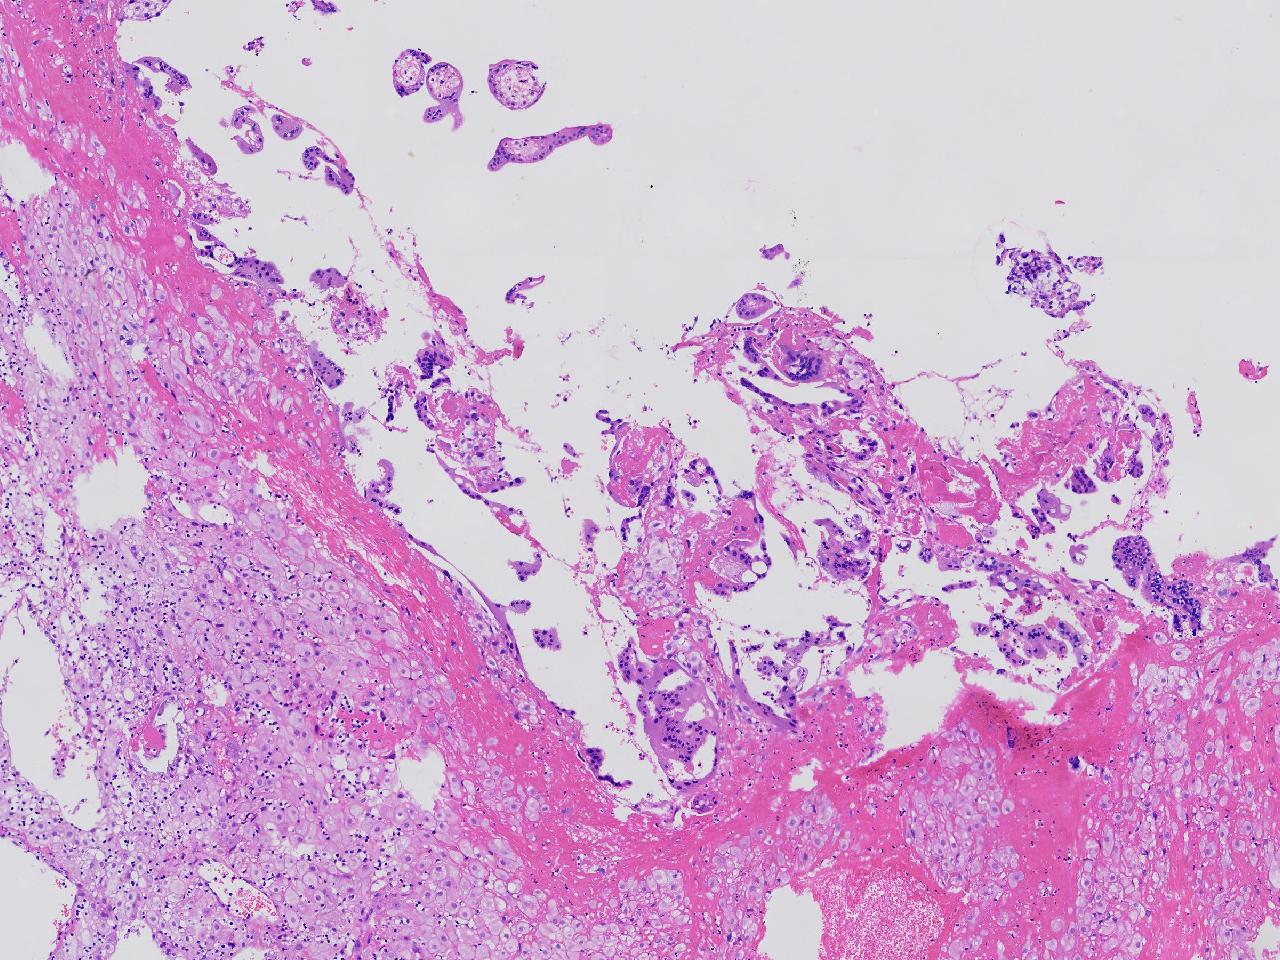

女,29岁,药物流产20余天,阴道少量出血20余天。行诊刮术。

宫腔内容物

灰粉色不整形软组织多块,4X3X3厘米,部分为血凝块。

送检组织为胎盘绒毛及蜕膜组织及滋养层细胞考虑为不全流产